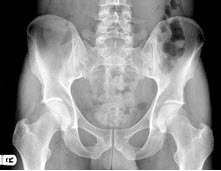

229、单项选择题

右髋关节疼痛,跛行1年多,无明显外伤史,双髋关节摄片如图,最可能的诊断是()

A.右髋关节退行性关节病

B.右髋关节创伤性关节病

C.右髋关节结核

D.右髋关节化脓性关节炎

E.右髋关节神经性关节炎